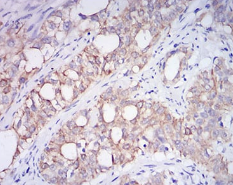

CD10 Mouse Monoclonal antibody[7D4B1]

This gene encodes a common acute lymphocytic leukemia antigen that is an important cell surface marker in the diagnosis of human acute lymphocytic leukemia (ALL). This protein is present on leukemic cells of pre-B phenotype, which represent 85% of cases of ALL. This protein is not restricted to leukemic cells, however, and is found on a variety of normal tissues. It is a glycoprotein that is particularly abundant in kidney, where it is present on the brush border of proximal tubules and on glomerular epithelium. The protein is a neutral endopeptidase that cleaves peptides at the amino side of hydrophobic residues and inactivates several peptide hormones including glucagon, enkephalins, substance P, neurotensin, oxytocin, and bradykinin. This gene, which encodes a 100-kD type II transmembrane glycoprotein, exists in a single copy of greater than 45 kb. The 5' untranslated region of this gene is alternatively spliced, resulting in four separate mRNA transcripts. The coding region is not affected by alternative splicing.

Immunogen:    Purified recombinant fragment of human CD10 (AA: 52-246) expressed in E. Coli.

IHC    1/200 - 1/1000